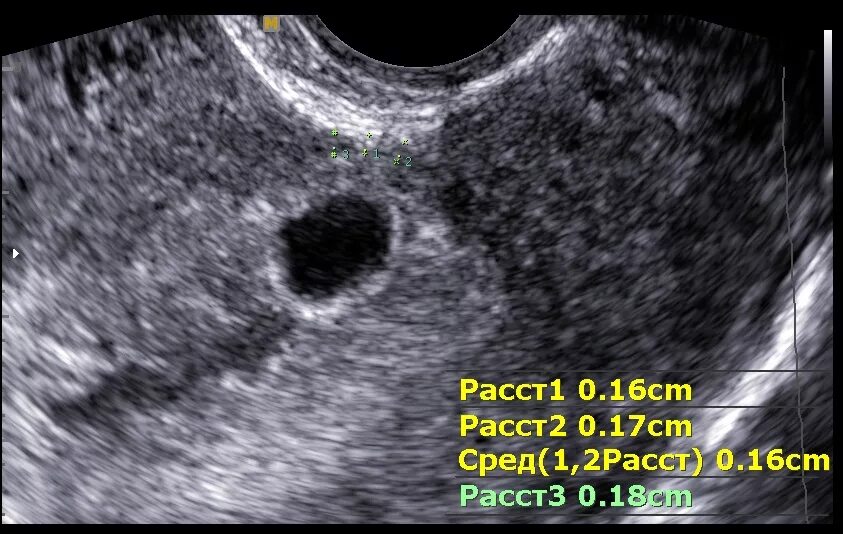

Можно ли забеременеть при полипе в матке